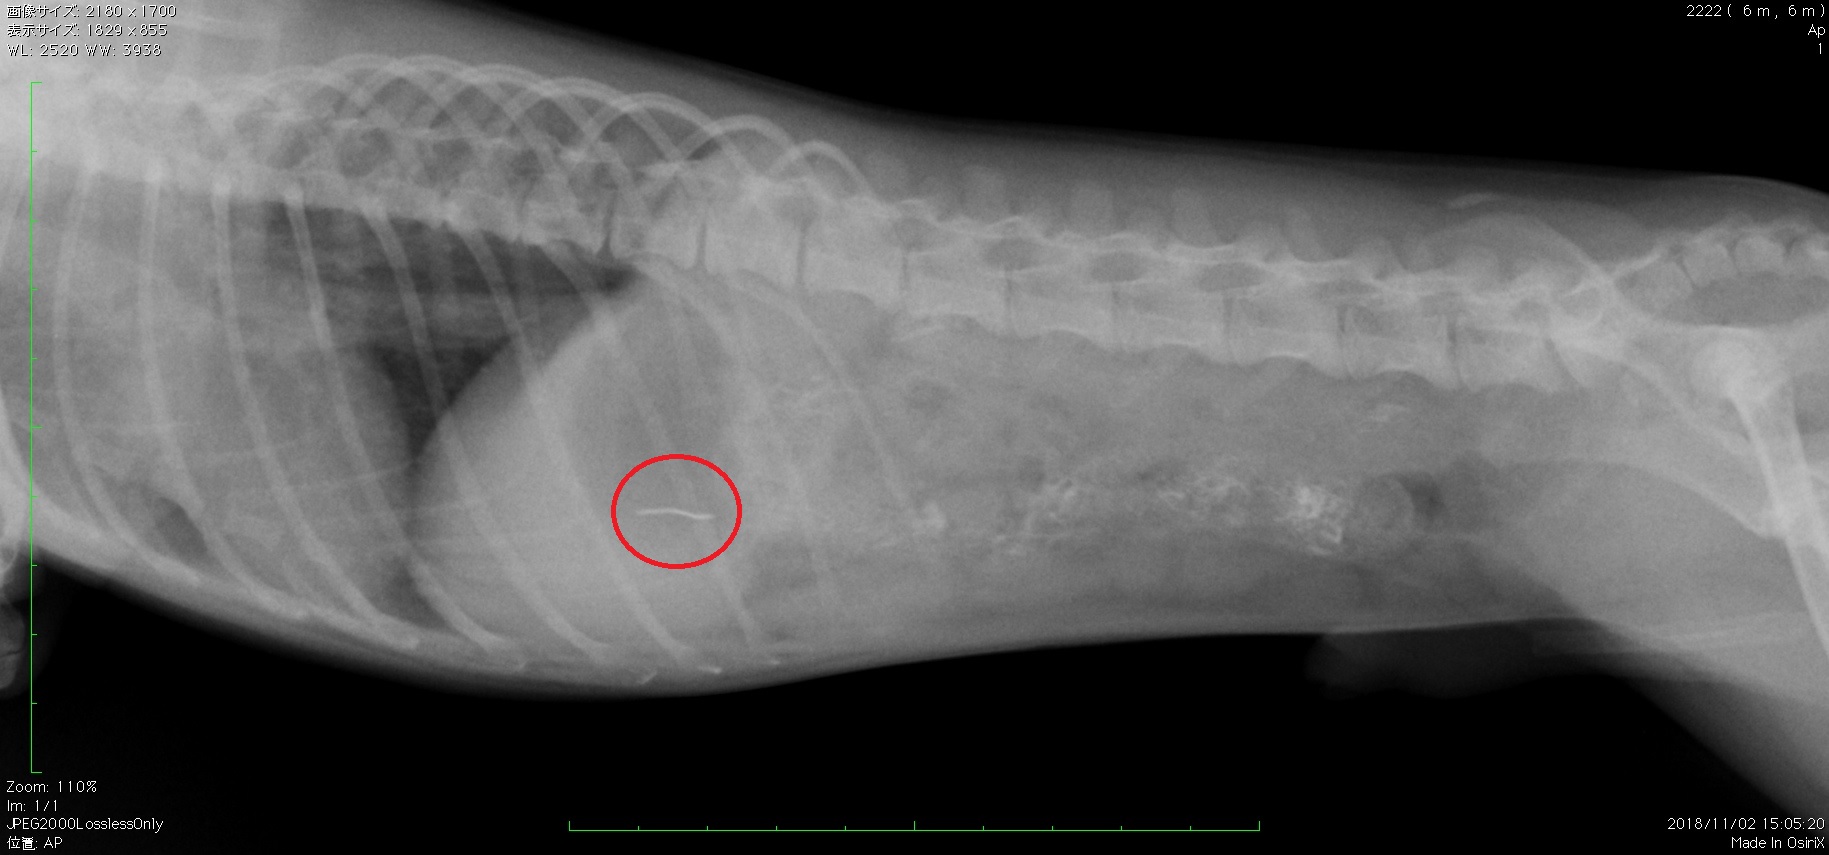

異物 縫い針 の誤食 淀川中央動物病院